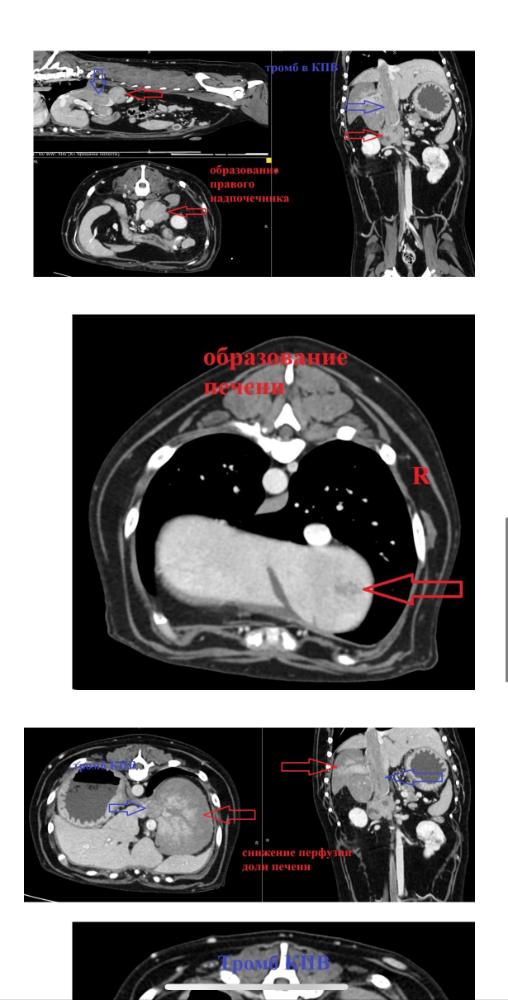

Дорогие форумчане, с Вилли случилась беда!!!🆘

Вилли разбил инсульт, 23.02 мальчик встал на кровати, пошатываясь, попытался спрыгнуть, но потерял сознание и нырнул в бессознательном состоянии на пол, тывнувшись носом с этой высоты в пол ((( Выбито 4 зуба. Сделали еще УЗИ - нашли образования в надпочечнике и печени, еще разные вопросы. 😔 Целый букет!

Сейчас мальчик был на КТ, ждем результаты. Когда падал с кровати без сознания, сломал об пол 4 зуба. Удалили их под седацией сейчас, поскольку давать полноценный наркоз чревато. Теперь надо обращаться к терапевтам за грамотной терапией, чтобы поддержать ребенка на сколько возможно. Там букет, боюсь, что на КТ откроется еще более страшная картина.

Получили описание  КТ и свежие анализы крови 😔 Множество образований, показатели крови ухудшаются...